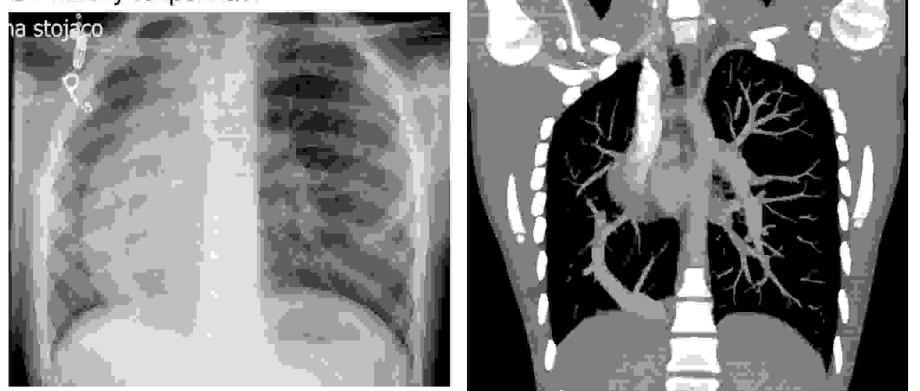

Na podstawie zamieszczonych poniżej RTG klatki piersiowej oraz angio-CT należy rozpoznać:

Pytanie 18